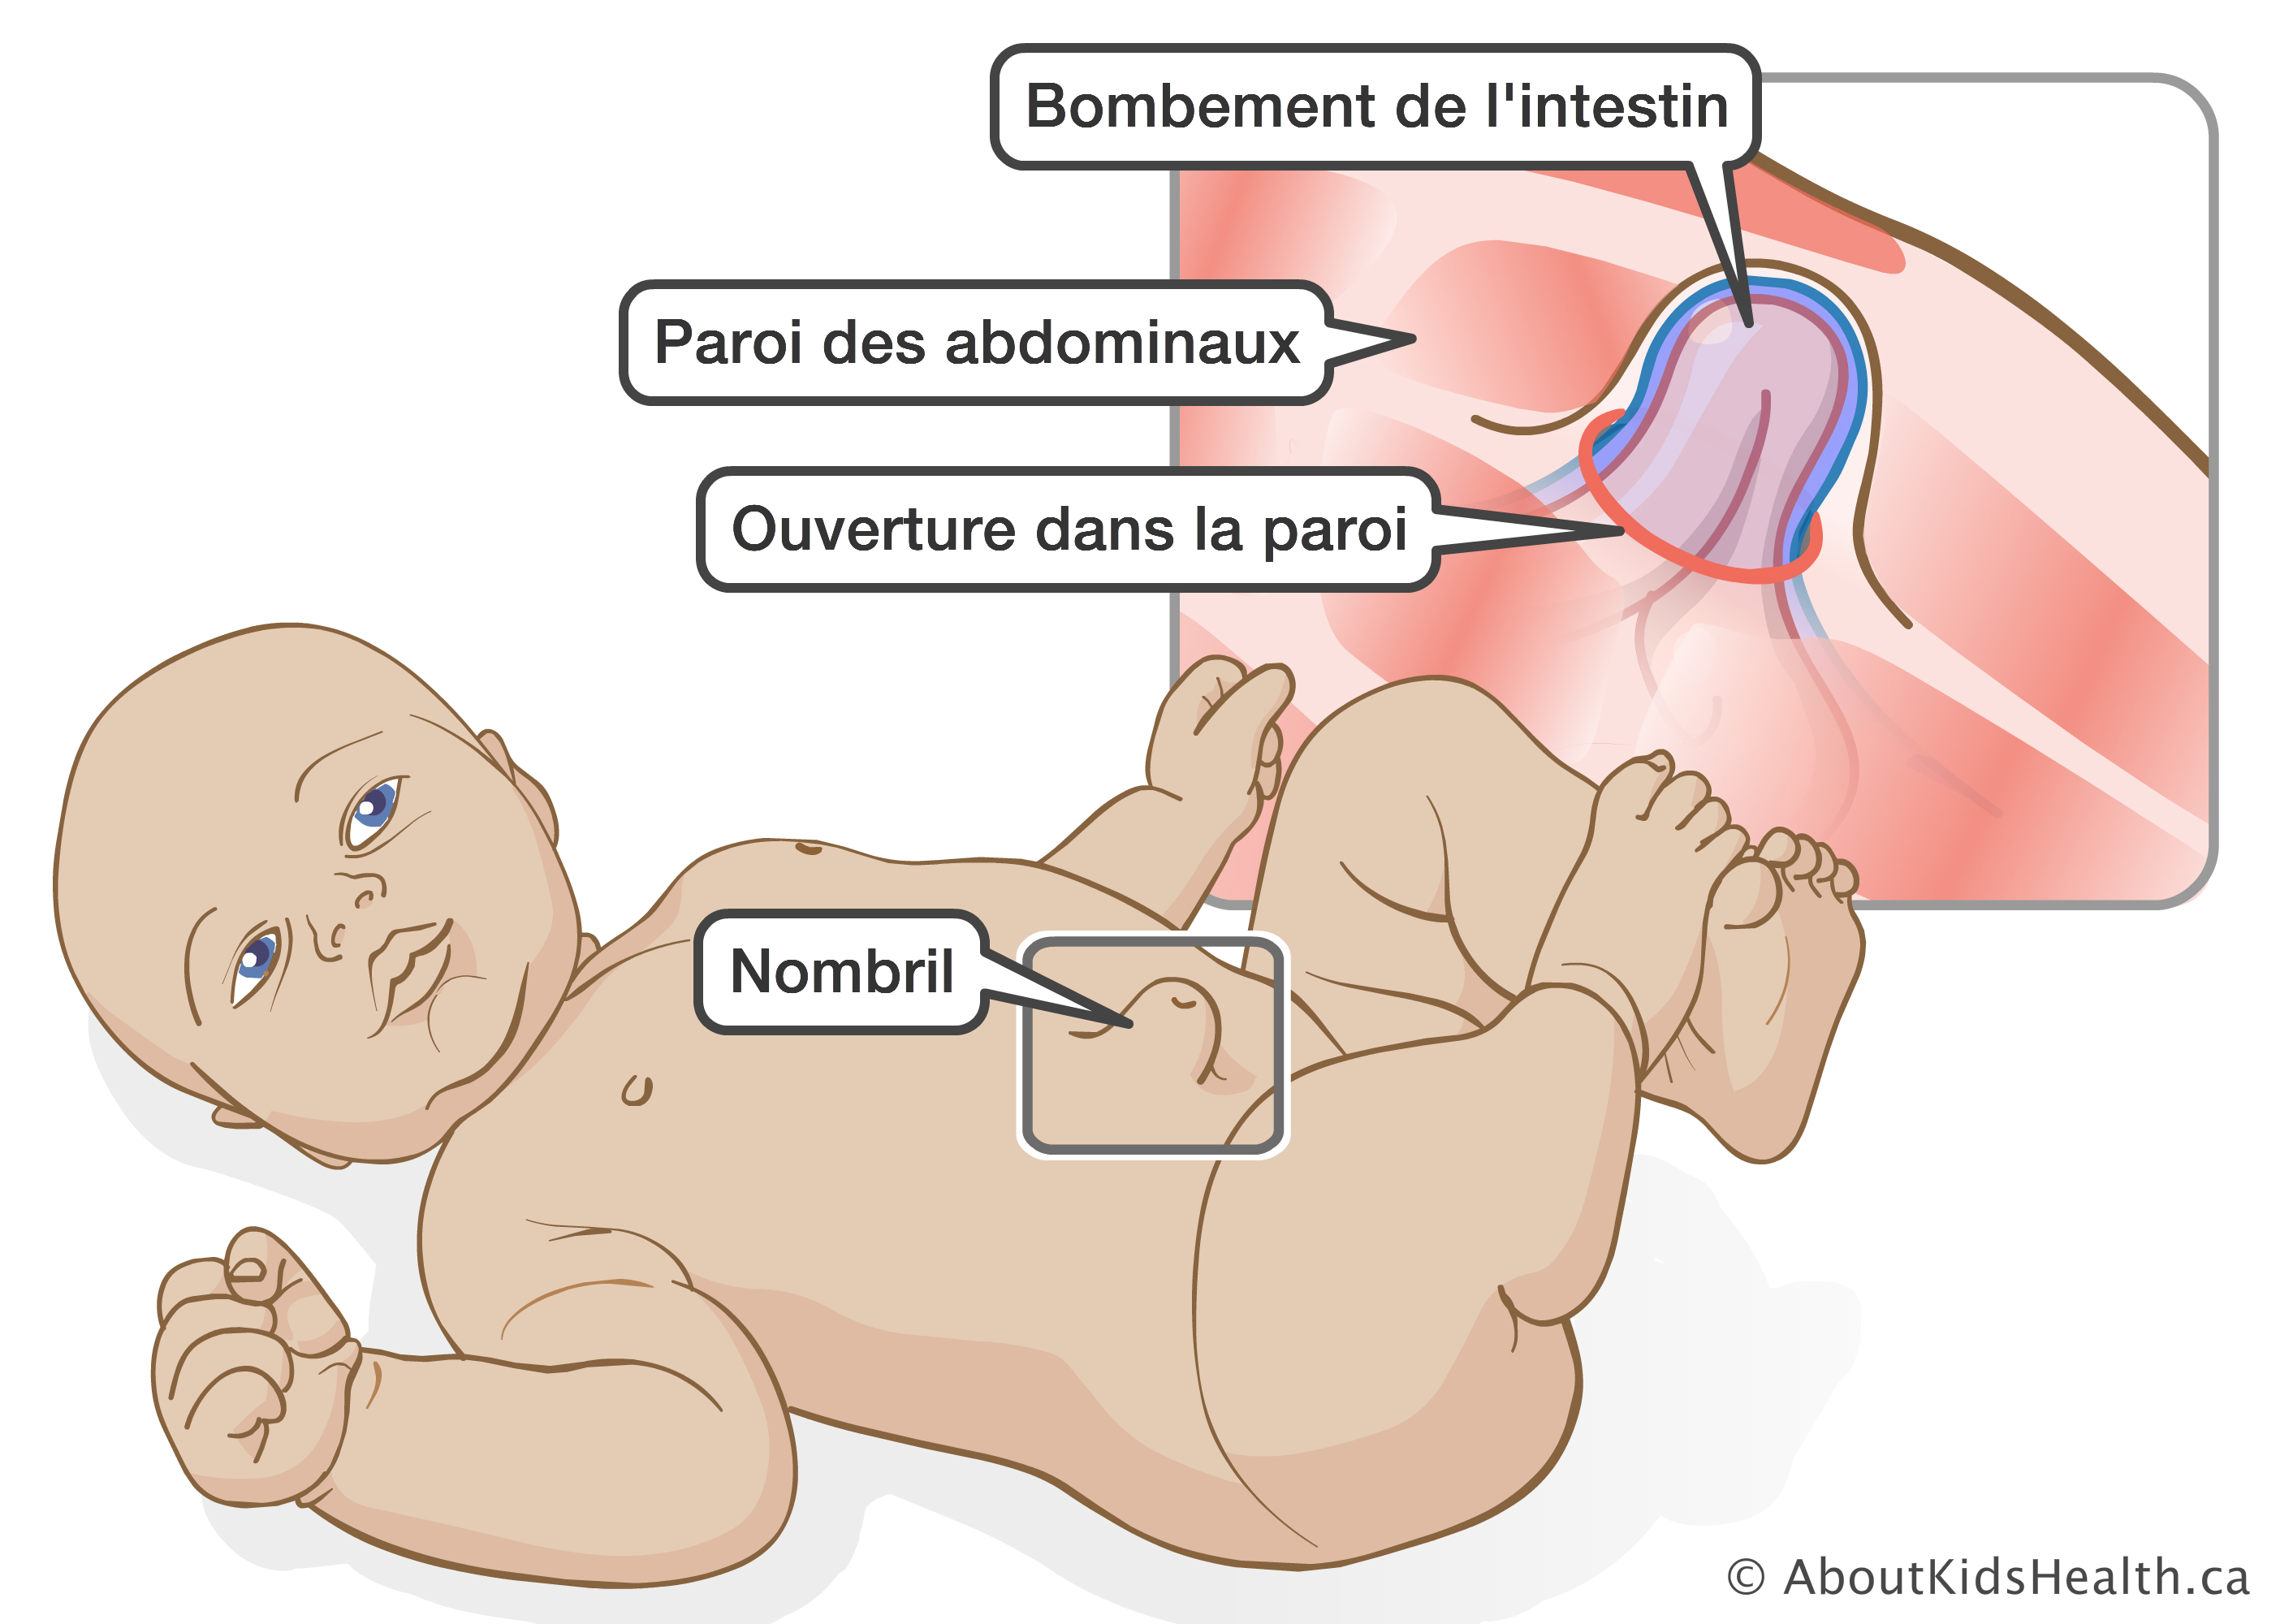

Чаще всего грыжа возникает вследствие дефекта передней брюшной стенки, слабости пупочного кольца. Провоцирующим моментом является длительное повышение внутрибрюшного давления в результате сильного кашля, запоров, продолжительного плача. Такие заболевания, как рахит, гипотрофия, снижающие тонус мышц, создают благоприятные условия для образования пупочной грыжи. Наиболее часто грыжа встречается у недоношенных детей. В пупочную грыжу обычно выпадают петли кишечника ребенка или сальника.

Грыжа

Самое частое объяснение того, что у ребенка может выпятиться пупок, – это грыжа. Обычно она носит врожденный характер и становится заметной на втором месяце жизни крохи. В норме после обрезания пуповины пупочное кольцо стягивается, сжимается. Если этого не происходит, или оно не закрывается до конца, формируется выпячивание. Особенно оно заметно, когда ребенок плачет или кашляет. Любое напряжение мышц живота выдает грыжу. Причем в обычном состоянии, когда малыш лежит, он спокоен, она может и не выдавать себя.

Образование врожденной грыжи. Как уже было сказано, поводом для образования грыжи является ослабление брюшной стенки. И существуют определенные причины, по которым ее формирование в утробе матери происходит не так, как это необходимо. А главной причиной слабости брюшины становится недостаточная прочность мышечной структуры и соединительных тканей — поэтому брюшина начинает развиваться с дефектами. В результате грыжевое образование возникает еще до рождения ребенка, ведь в утробе матери внутренние органы уже начинают оказывать давление на место соединения с пуповинным канатиком.

Пупочная грыжа у новорожденных может быть прямой или косой. В первом случае грыжевой мешочек и его составляющие просто выходят за пределы пупочного кольца. Во втором — возникает более сложная структура: грыжевой мешок сначала оказывается в просвете между поперечной фасцией и белой линией живота, а затем выводится в пупочное кольцо.

Схематическое изображение выпирания кишки в область пупка. Пупочная грыжа.

Схематическое изображение выпирания кишки в область пупка. Пупочная грыжа.